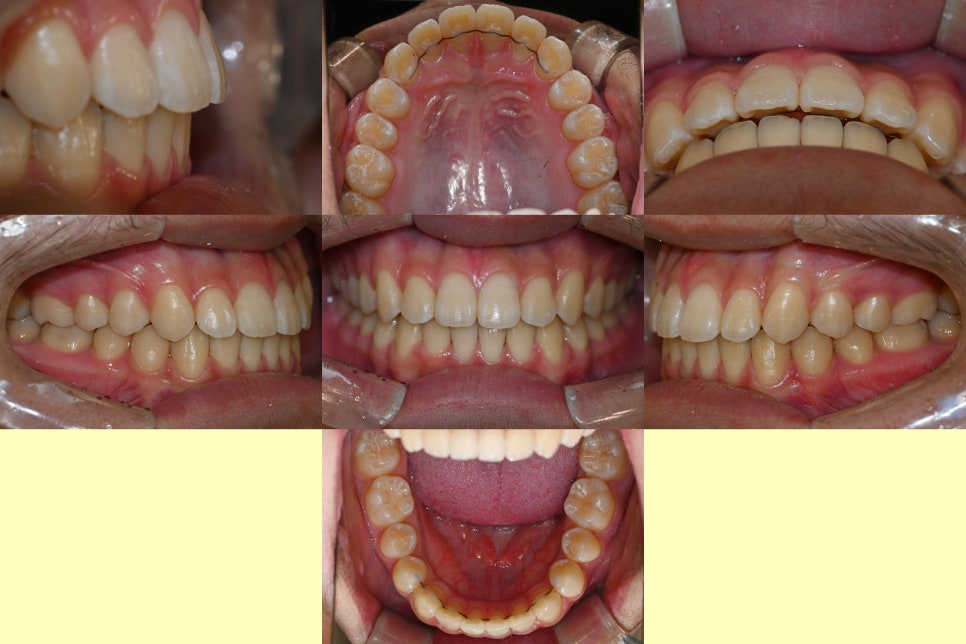

25.01.14

다음은 교정 후 모습입니다.

앞니 사이 벌어짐 과 뻐드러짐 이

단번에 개선되면서 치아각도도

올바르게 세워졌습니다.

앞니가 가지런하게

안쪽으로 모이면서 안모에도

좋은 변화가 찾아왔습니다.^^